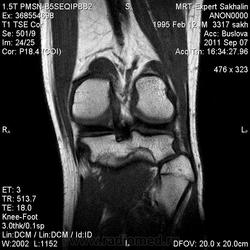

МРТ коленного сустава.Остеома малоберцовой кости?

Сегодня был молодой человек без направления.Принес диск КТ-исследования  коленных суставов от 2010 года.Заинтересовала малоберцовая кость.

И клиника какая? Болезненность есть? По МР-сигналу если все вышеизложенное исключается больше данных за остеохондрому, (экзофитное расположение, сигнальные характеристики костного мозга)

Не знаю-может быть и вариант строения.Но правая малоберцовая кость не изменена.Кортикальный слой не нарушен.Как мне показалось-по сравнению с КТ-исследованием без динамики.

Склоняюсь к остеохондроме.

КХЭ с неоартрозом с большеберцевой костью и деф. артрозом в этом суставе...  Но экзостозы обычно множественные...

Нет, Анатолий Владимирович, экзостозы чаще солитарные. По МКБ "остеохондрома" и "множественные костно-хрящевые экзостозы" вообще разные нозологии.

Касательно данного случая. Думаю - остеохондрома.

Тем не менее, настоятельно призываю коллег придерживаться общепринятых (и у нас, и у буржуев) стандартов диагностики заболеваний костей. Согласно которым, основным методом диагностики является обычная рентгенография. КТ- очень полезный дополнительный метод. МРТ - дополнительный метод, имеющий более узкие показания. МР-семиотика опухолей костей в достаточной мере не разработана, поэтому в костной патологии не стоит делать заключения только по МРТ, без данных рентгенографии или КТ